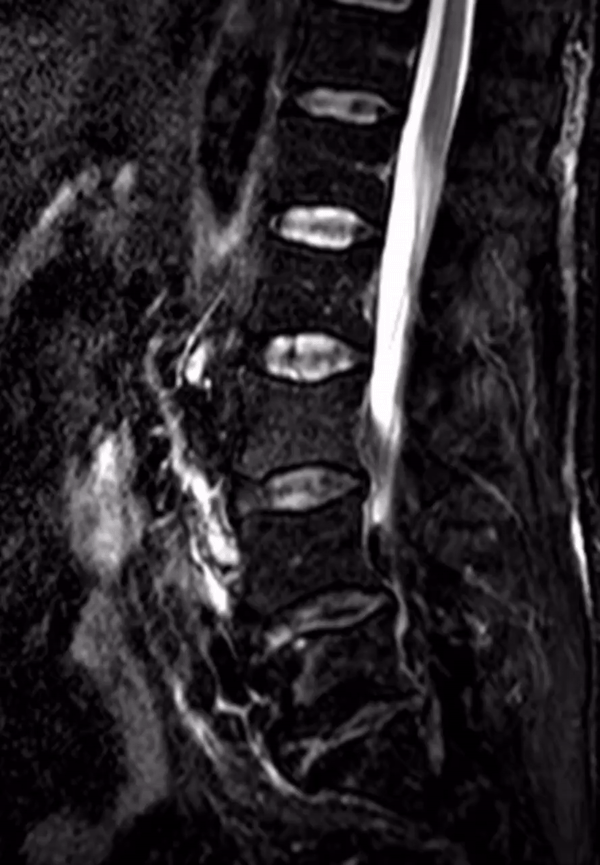

If we look at a lateral STIR sequence of the lumbar spine, we can see high signal in the lateral aspect of the L3-4 disc which is continuous with the abscess formation within the right psoas. This highly suggests a spondylodiscitis as the primary pathology leading to secondary psoas abscess.

When we scroll through this sagittal STIR sequence of the lumbar spine we will see high signal within the L3-4 disc adjacent to the right psoas abnormality.